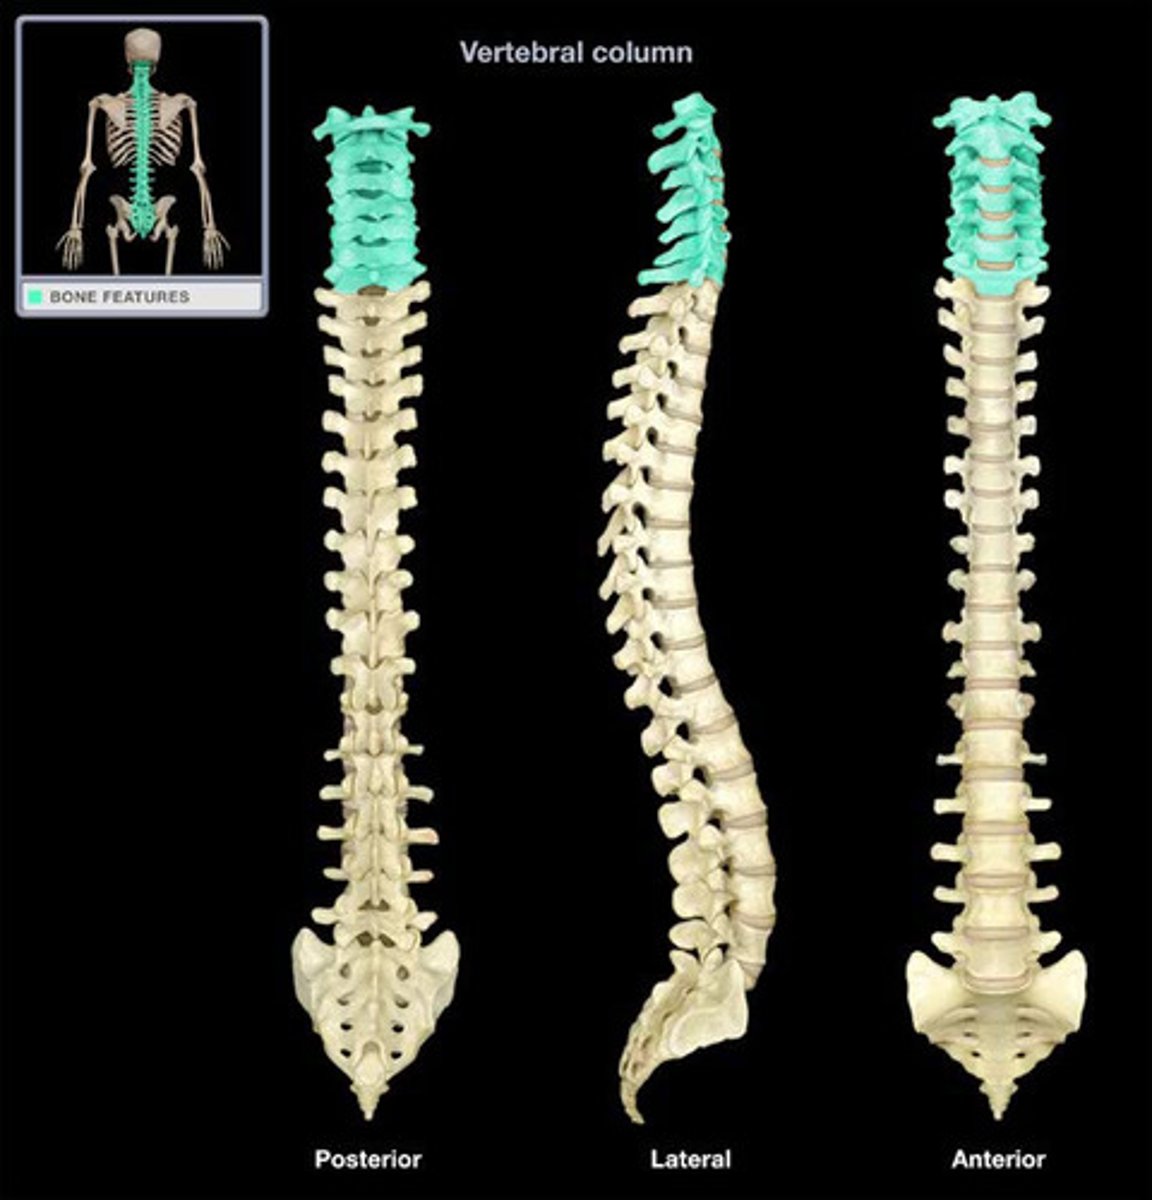

Cervical Vertebrae 7

Atlas

Axis (C2)

Thoracic Vertebrae 12

Lumbar Vertebrae 5

Sacrum 5 fused

Coccyx 3-5